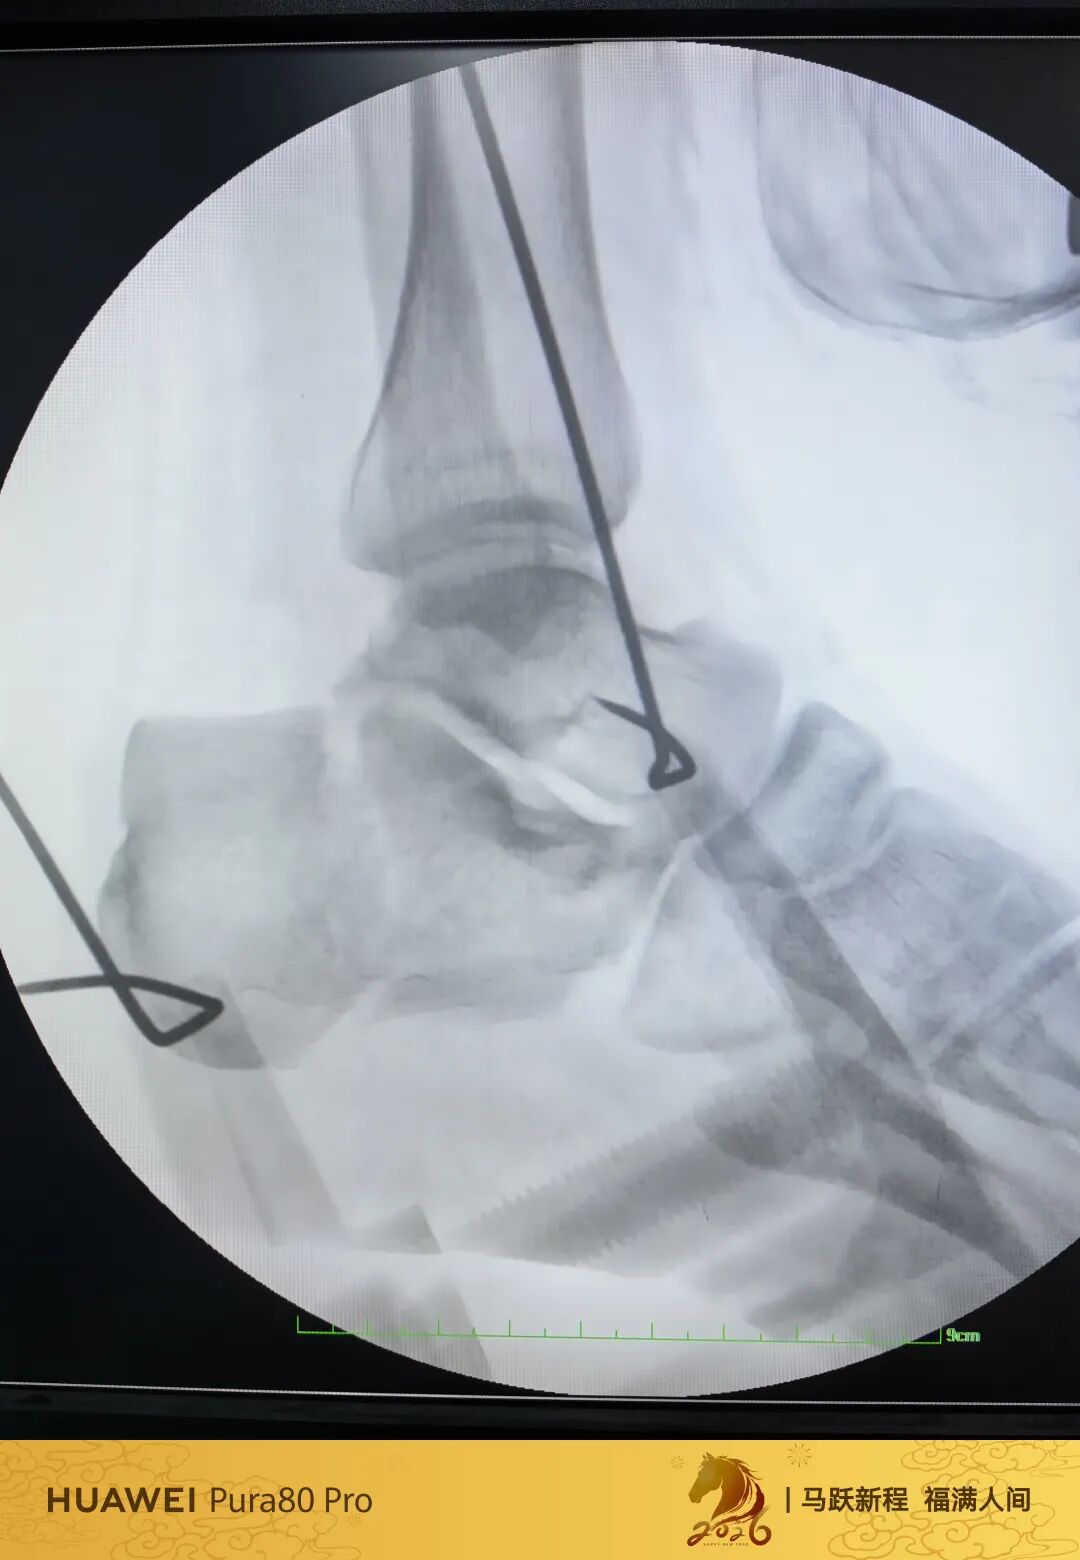

第60例跟骨微创了,虽然已经彻底放手,尽量只动嘴,但还是有小问题小瑕疵,无法完全避免。